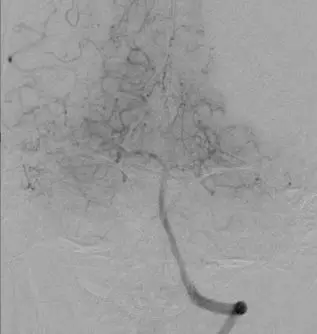

颈内动脉DSA提示颅内存在三处病变血管:大脑中动脉上干闭塞,下干的起始段局部有血栓形成以及一支M2段分支闭塞。

使用Navien导管回收保护伞,快速建立取栓通道。

使用4-20 Solitaire 支架进行MCA下干取栓。

下干取栓后DSA可见下干开通,M2分支以及大脑中动脉上干部分开通。

使用4-20 Solitaire 支架进行MCA上干取栓。 取栓后DSA提示上干完全再通,M2远端分支仍闭塞。

使用4-20 Solitaire 支架进行M2远端分支取栓。 取栓后DSA提示三支病变血管均完全开通。